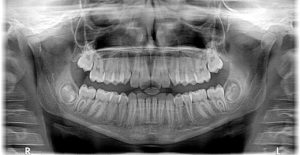

X-Rays Taken

Necessary x-rays will be taken.